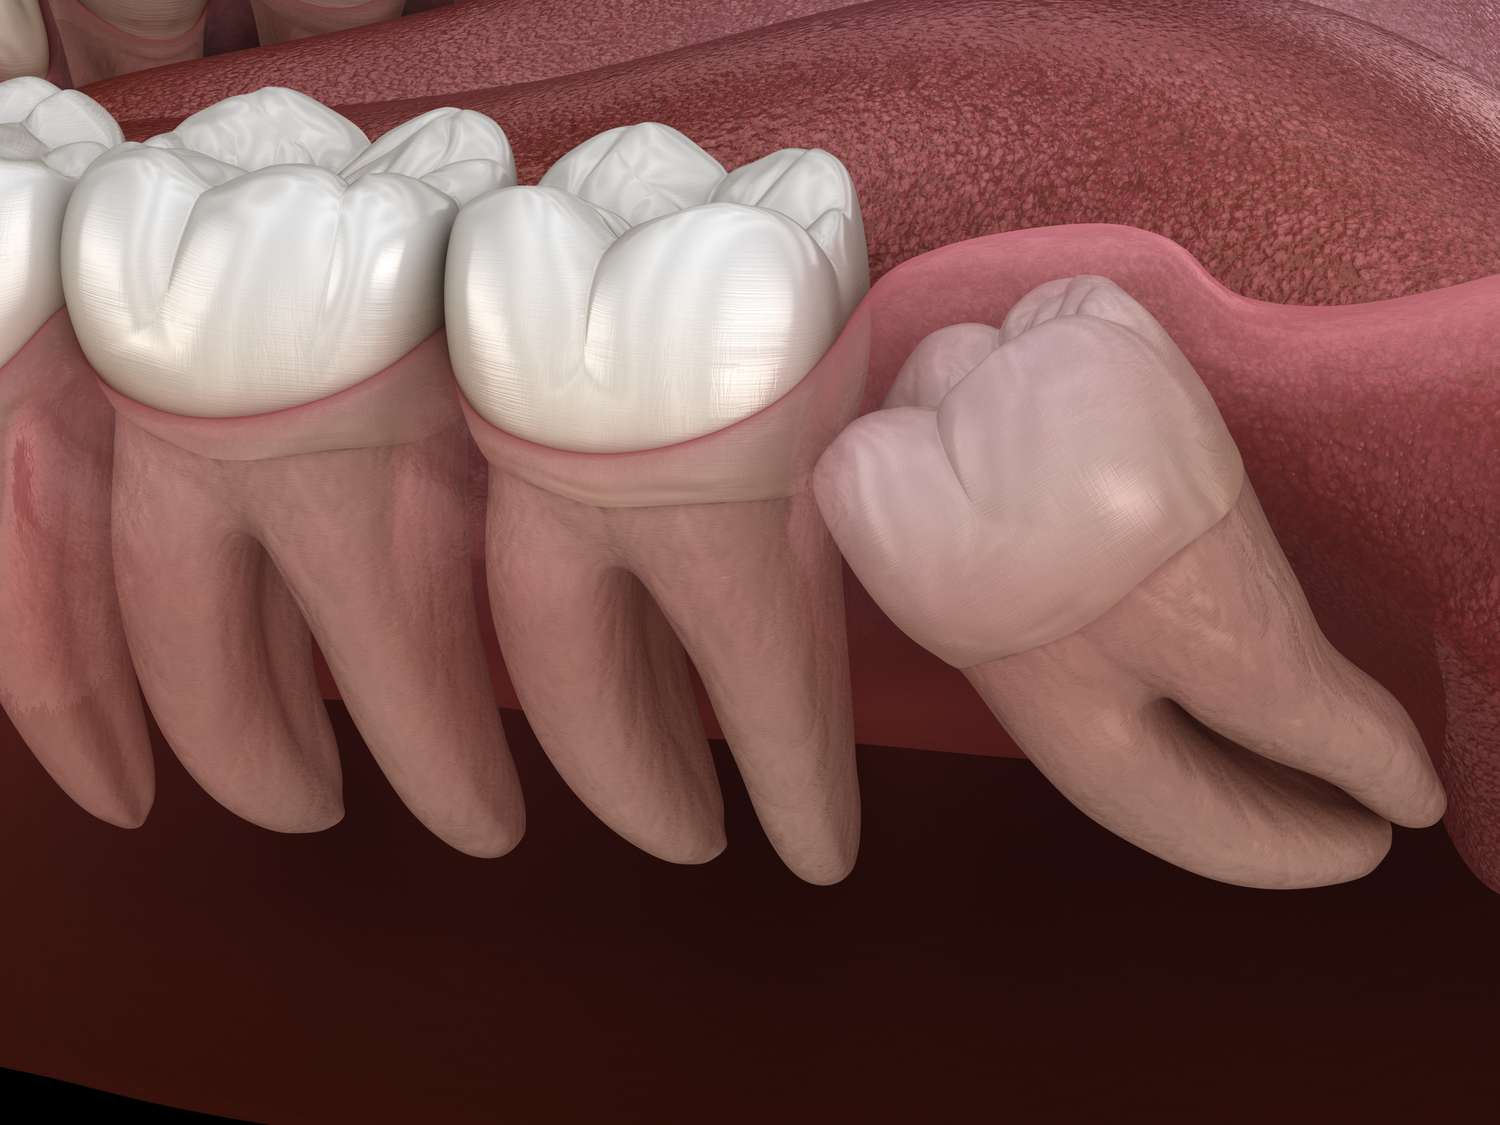

The most common reason for wisdom teeth extractions is insufficient space in the mouth. When there is not enough room for the wisdom teeth to emerge properly, they may become impacted, meaning they cannot fully break through the gum line. Impacted wisdom teeth can lead to various issues, including pain, infection, and damage to neighboring teeth.

Wisdom teeth may erupt at awkward angles or positions, causing them to press against neighboring teeth. This misalignment can result in crowding and disrupt the alignment of your existing teeth.